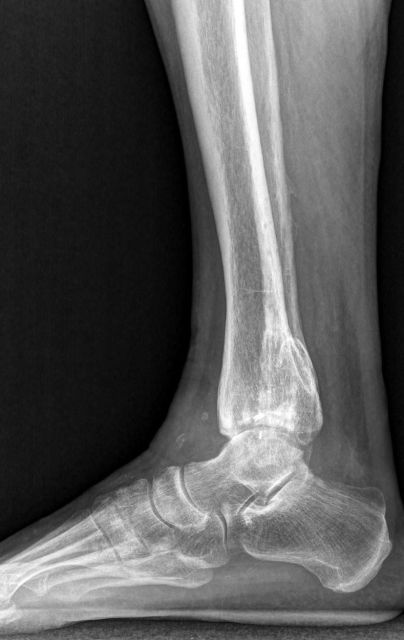

Bei Patienten mit schwerer Degeneration des Sprunggelenks (Arthrose) sind typische Symptome Schmerzen, fehlende Stabilität, Reduktion der Gehfähigkeit, Verschlechterung des Bewegungsumfanges des Sprunggelenks und oft auch zunehmende Fehlstellung des gesamten Fußes (X-Bein, O-Beinfehlstellung). Bei leichteren Formen leiden die Patienten unter Belastungsschmerzen, während bei fortgeschrittener Arthrose die Schmerzen auch in Ruhe auftreten.

OSG-TP vorher-nachher